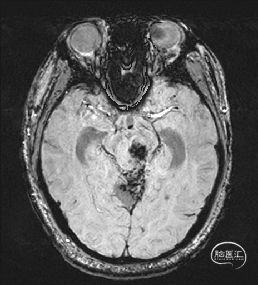

术前MRI检查

术前MRI检查提示左侧丘脑中脑海绵状血管瘤并卒中,梗阻性脑积水;

诊断:1.左侧丘脑中脑海绵状血管瘤并卒中,2.梗阻性脑积水;

年轻患者,较短时间内发生左侧丘脑二次出血,出现右侧面部及上肢麻木,复视,第二次出血后并发梗阻性脑积水,出现头痛。结合病史、神经系统体征、头颅CT及MRI检查,诊断左侧丘脑及中脑CM并卒中、脑积水明确,并导致了神经功能障碍,具备手术指征。

根据MRI及DTI显示,只有在丘脑与上丘之间的点(dot)进入病变才可能在切除病变时最大程度保护神经功能,由于上述原因,该“点”在术中显露极其困难,虽有导航指引,电生理监测的条件下,对术者的耐心、技术、经验及体能依然是极大的挑战;

本例患者磁共振检查清晰显示病变位于左侧丘脑中脑区域,且位于丘脑内下方向中脑顶盖延续,病变的上部、前部、外侧部都有重要的神经组织,因此,手术从上方、前方、外侧方向切除病变均难以实施;